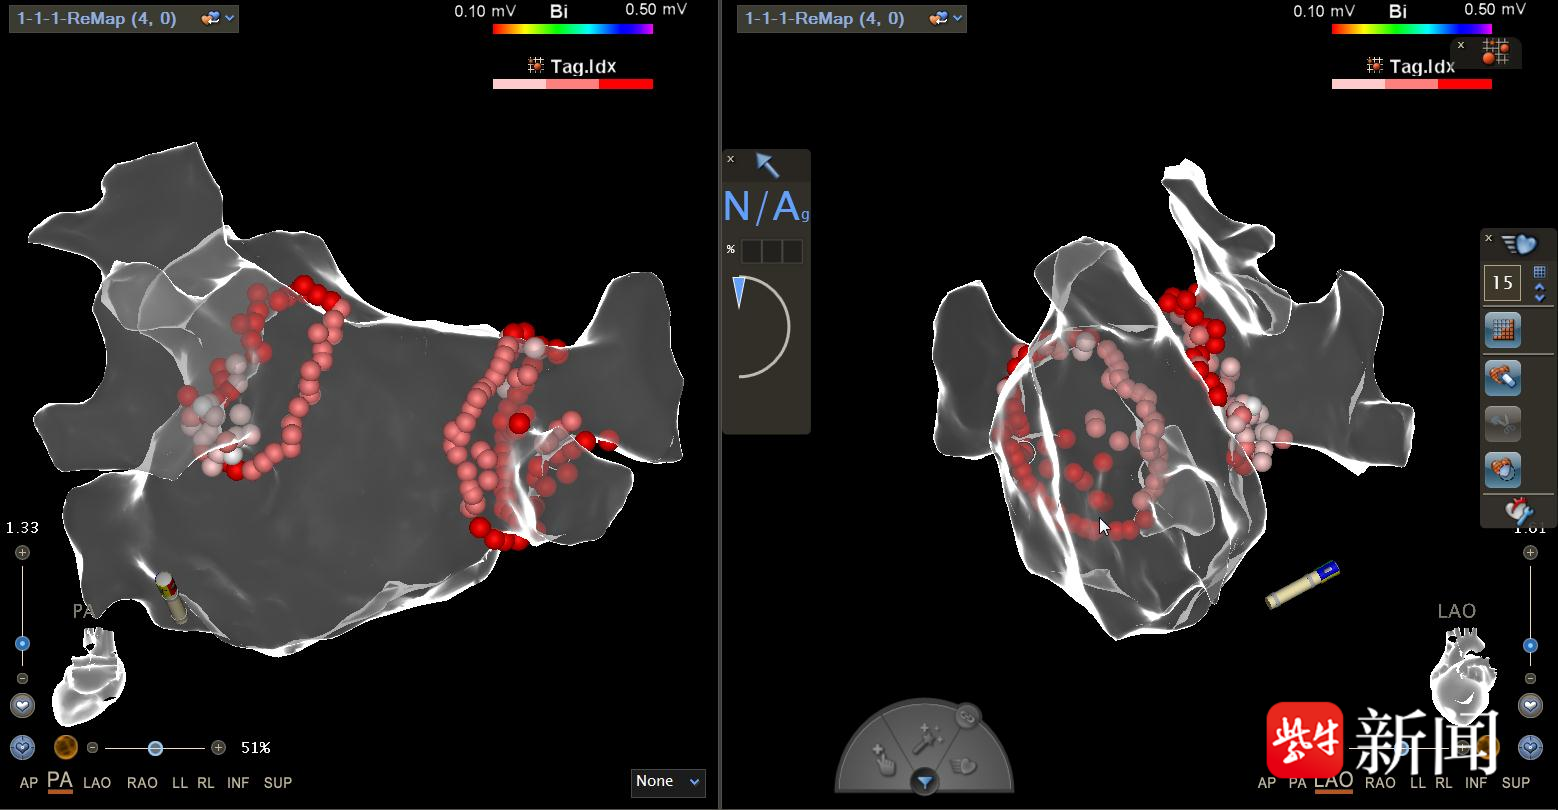

可惜1年后,王奶奶房颤复发,陈主任告诉她,电复律虽然能快速转复心律、缓解房颤带来的不适,但多数人难以长期维持,每日服药也会给身体带来一定副作用。为不再经受心慌胸闷的痛苦,经过充分沟通,老人接受以环肺静脉电隔离术为基础的房颤射频消融手术,术后规律服用抗凝+抗心律失常药物以及科室特色中药宽心宁悸方3个月并严格随访。如今,王奶奶仅需每日服用降压药和小剂量阿司匹林,一年多来房颤未再复发,心慌、胸闷等症状也彻底消失,生活质量明显改善。